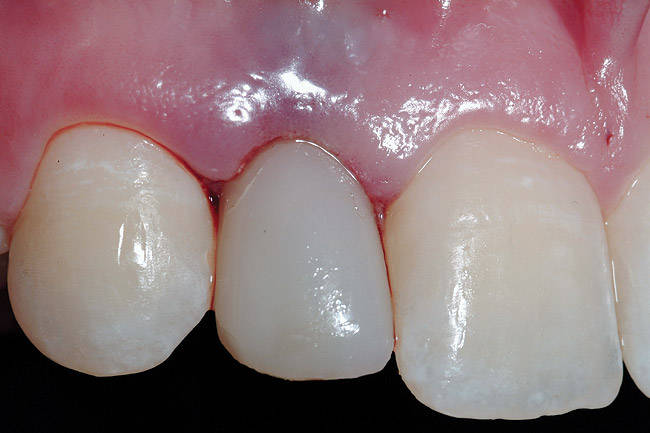

Figure 14  Immediate postoperative view; right lateral incisor.

Figure 14

Figure 15  Immediate postoperative view; left lateral incisor.

Figure 15

Conversion of the surgical guide to the esthetic provisional was then completed by retrofitting the surgical guide with restorative composite, and then placing the guide back over the provisional copings that were seated on the abutment portion of the one-piece implants, and curing the surgical guide with a curing light (Figure 12). The guide was then reviewed, with the provisionals in the guide, then removal of the provisionals from the vacuform portion of the guide allowed for correction of the marginal portion of the provisionals using a flowable composite material. Shaping the line angles and emergence profile of the provisionals allowed for the proper contours of the provisional to be accomplished (Figure 13). The provisionals were then cemented with a strong temporary cement. The immediate postoperative clinical view can be seen in Figure 14 and Figure 15. The provisionals were immediate, non-functional restorations in centric occlusion and relation, and lateral right and left excursive movements. Figure 16 and Figure 17 show the immediate postoperative radiographic view. Note how the 3-mm diameter implant allows for the adequate space between the root surfaces and the implants placed.